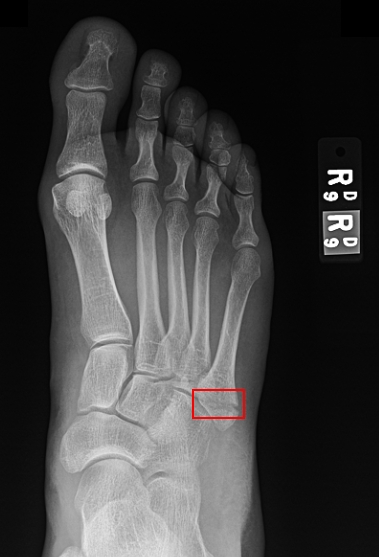

That night she was certainly having a lot of trouble hobbling around, and cried out a few times from pain, but she didn’t even take any Tylenol or anything. Even though it didn’t swell that much, we were still certain it was a sprain. In retrospect, all of the bruising and pain were localized to a *very specific* part of the foot, but hindsight is 20/20.

Her doctor finally called back 7 hours later and said she would take a look if Sara could come over right away (good thing she works at the hospital!). They decided to do x-rays, but didn’t think they’d be able to read them until the next day, so Sara started walking home. When she was halfway home, the doctor called back and said, “Your foot is broken, you have to come back to the hospital!”

We figured out later that between when she fell (about 3 p.m. on Thursday) and when it was diagnosed (about 5:30 p.m. on Friday), she walked about 5 miles on it.

The doctor said 6 – 8 weeks for the boot, which means it won’t be off before the baby is born. I’m not sure why adding a broken foot makes labor seem that much worse, but labor with a broken foot just seems that much worse.